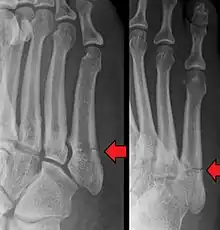

- Proximal diaphysis, typically stress fracture.[12][13]

- Metaphysis: Jones fracture[14]

-Tuberosity: Pseudo-Jones fracture[15] (avulsion fracture).[15]

Normal anatomy:

- Apophysis: Normal at 10 - 16 years.[16]

- Os vesalianum, an accessory bone.[17]

Other proximal fifth metatarsal fractures exist, although they are not as problematic as a Jones fracture. If the fracture enters the intermetatarsal joint, it is a Jones fracture. If, however, it enters the tarsometatarsal joint, then it is likely an avulsion fracture caused by pull from the fibularis brevis tendon. An avulsion fracture at the base of the fifth metatarsal is sometimes called a "dancer's fracture" or a "pseudo Jones fracture", and usually responds readily to non-operative treatment.[18] The X-ray appearance of the developmental "apophysis" in this area may have some resemblance of a fracture, but is not a fracture; it is the secondary ossification center of the metatarsal bone. It is a normal finding that occurs at this site in adolescents.[19] If an injury to that area has occurred, the physician is often able to interpret certain radiographic clues to make the differentiation. An avulsion fracture at this location is typically extra-articular and oriented transversally as compared to the longitudinal orientation of an unfused apophysis.[19]